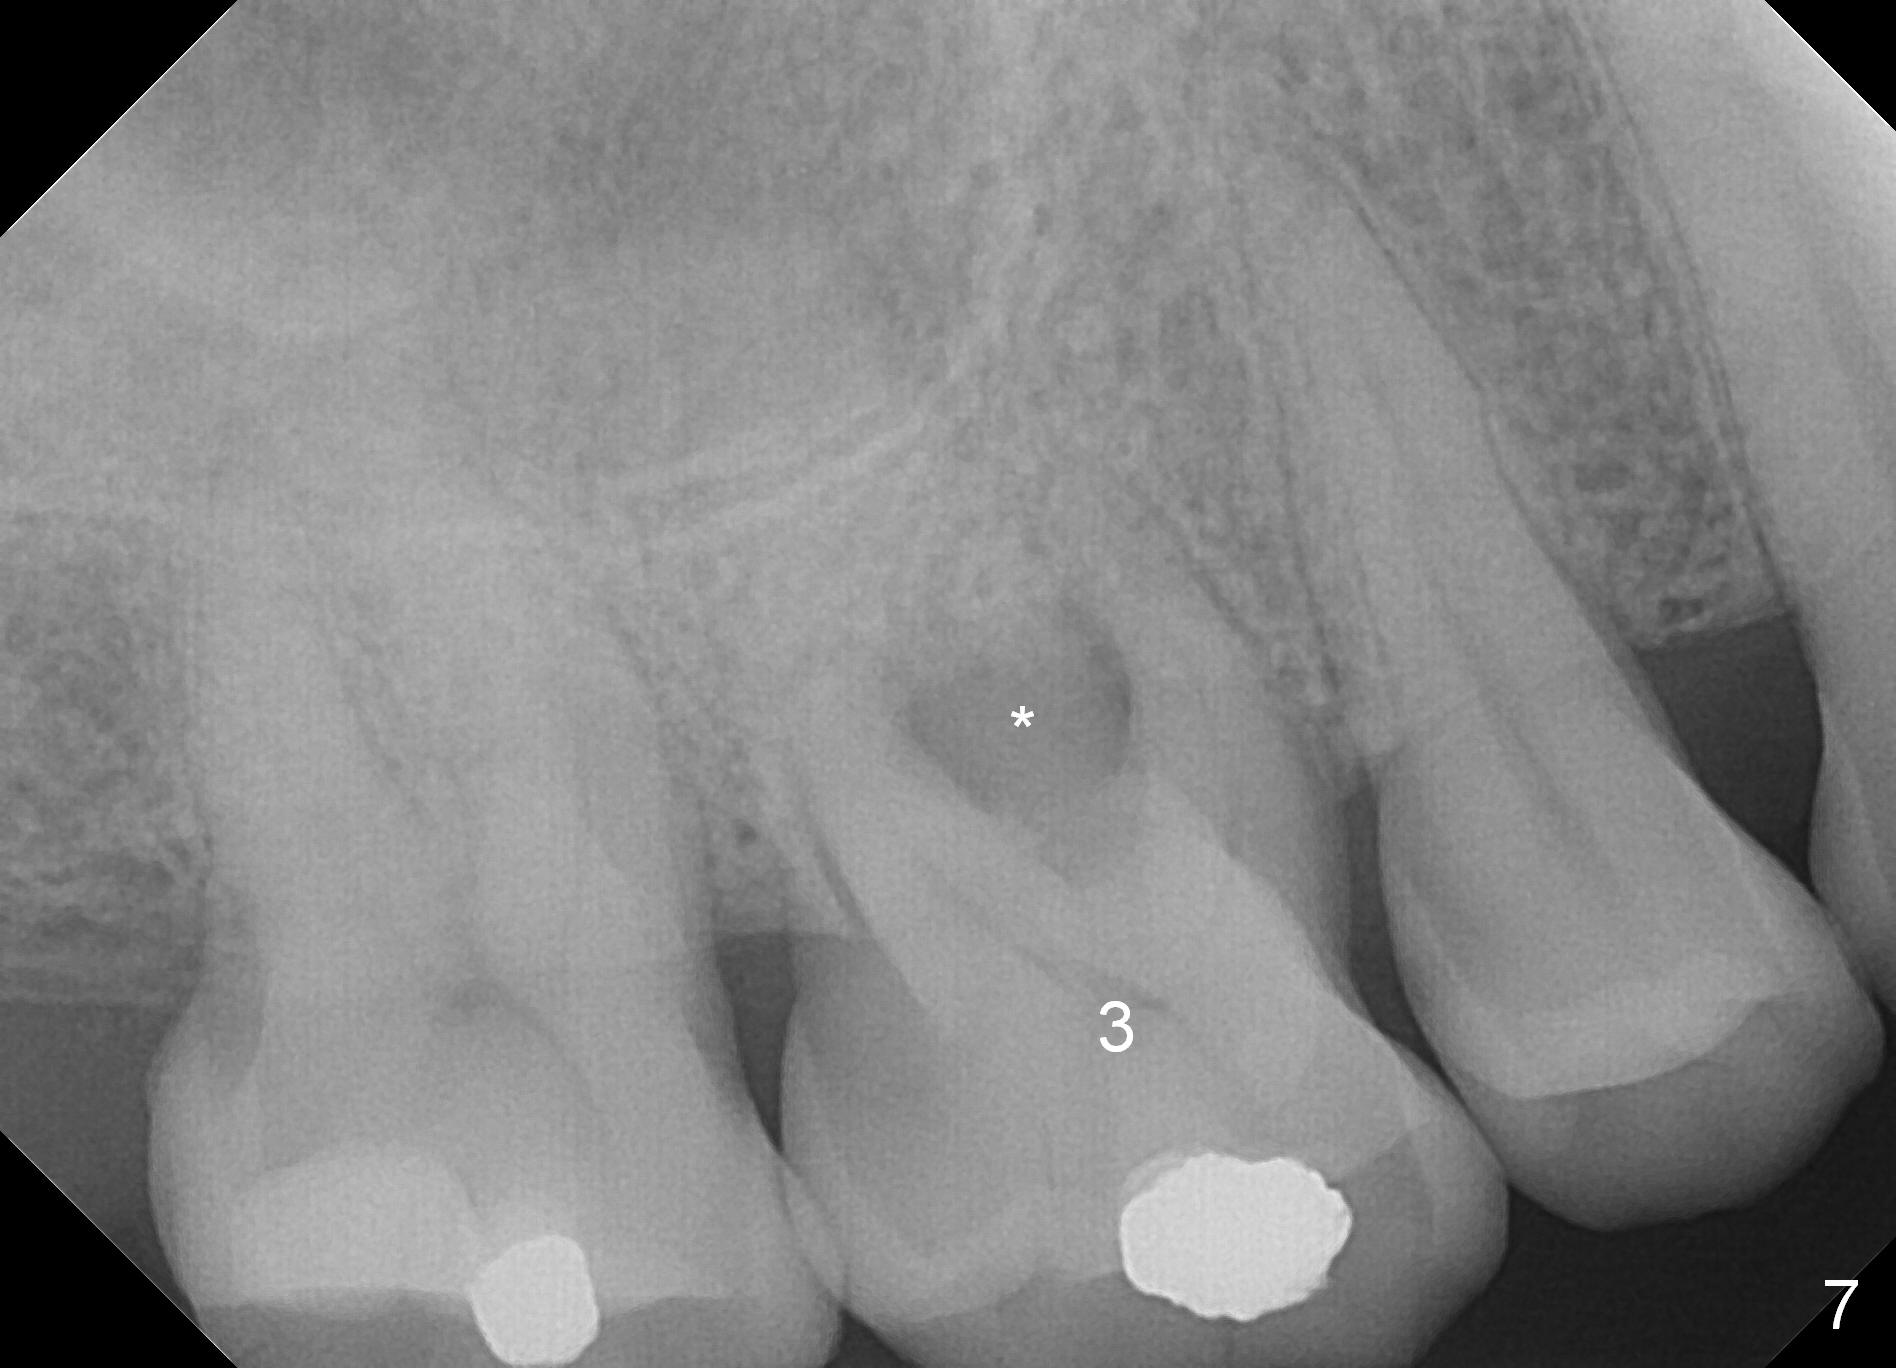

A 47-year-old man has history of bruxism, chipping porcelain from #29-31 FPD (Fig.1). Following sectioning the FPD, osteotomy is created (Fig.2: 5x14 mm drill) for placement of a 5x14 mm tissue-level implant (Fig.3,4). A 4x3 mm abutment (Fig.5 (lingual view) A) with 3 vertical slots (* for increased retention) is placed to retain periodontal dressing. The crown over the implant has dislodged 3 times over 28 months post cementation (Fig.6). It appears that the top of the abutment is too rounded. Clinical exam shows that the abutment height can be more, although the tooth #3 is supraerupted (Fig.7 (orthodontic intrusion is not indicated because of furca infection)).

Pre-impression photos show supraerupted #3 (Fig.7). Clearance is a little more than 1 mm between the mesiopalatal cusp of #3 (Fig.7 *) and the rounded abutment (Fig.8). Removal of the abutment turns out to be easy. Reduction is confined to the opposing tooth (slopes of the cusps). No occlusal reduction is done for the new abutment as mentioned above except for 2 retention grooves. One-mm reduction ring barely passes the occlusal clearance (Fig.9). No cement is applied to the abutment in case a longer abutment may be required. Bone density seems to remain the same or increase after cementation of a new crown (Fig.7). The redo crown remains in place 1 year post cementation.